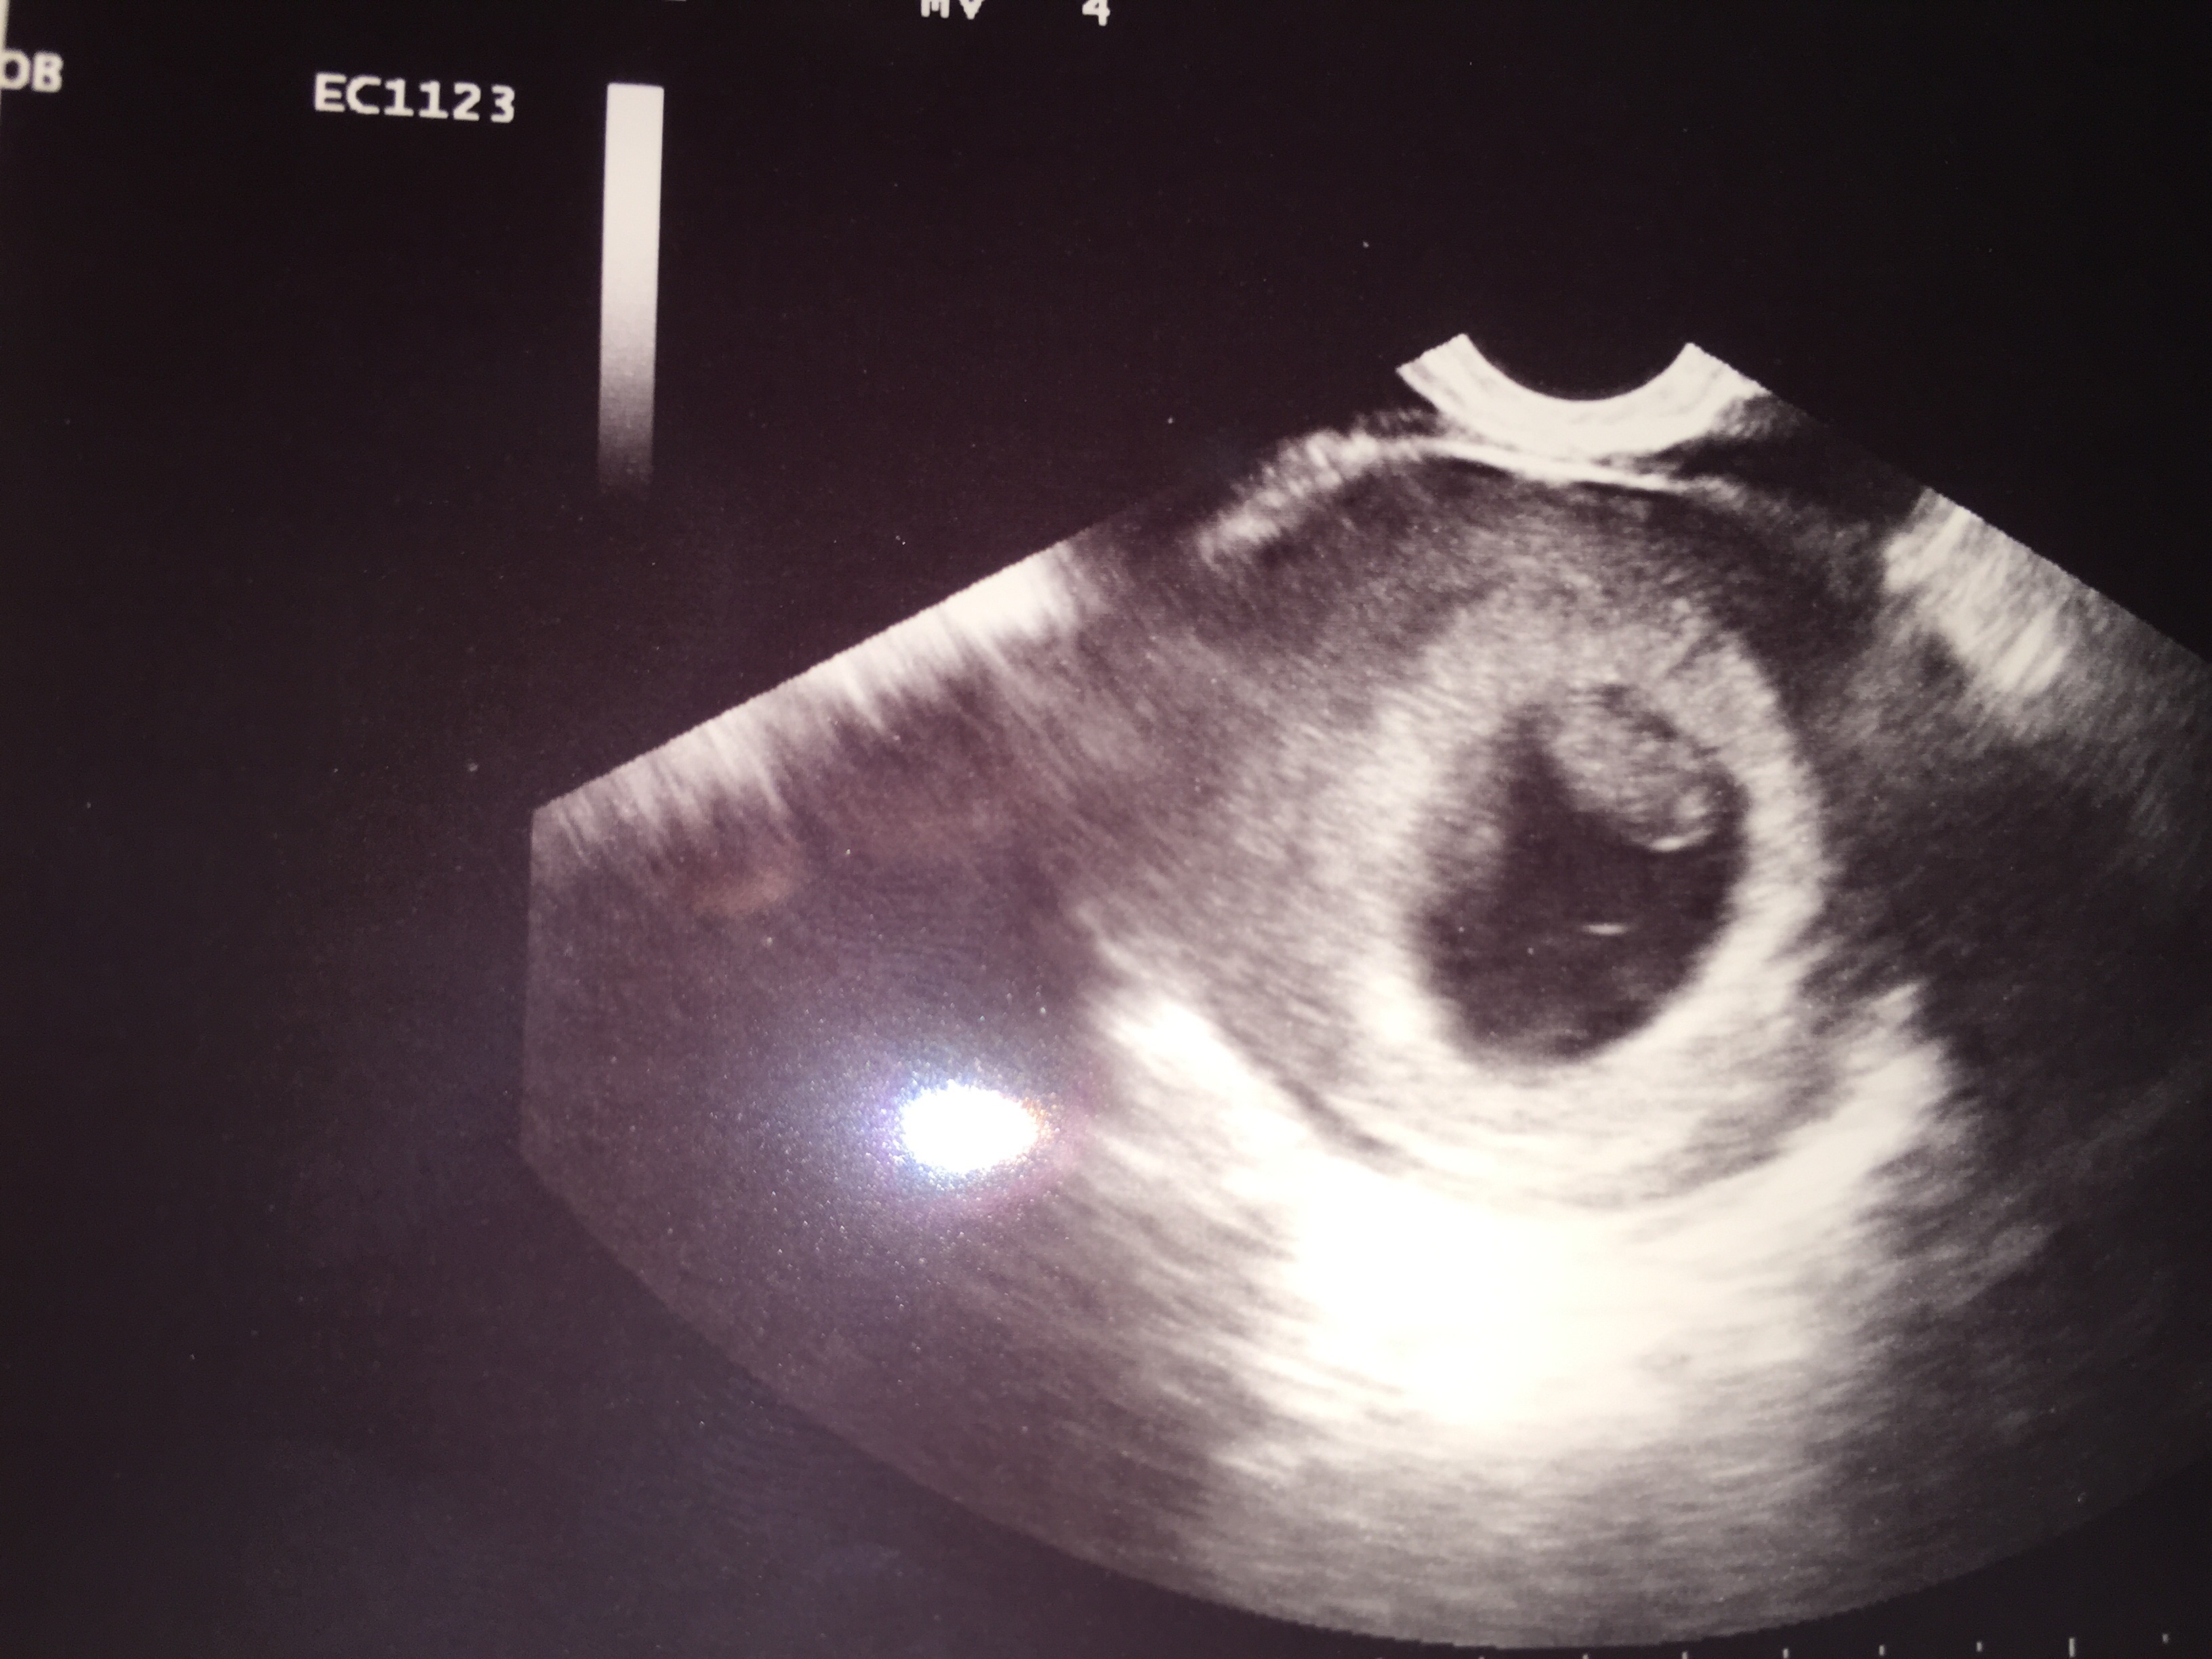

Mine is super hard to see, but what do you guys think? It was abdominal and the baby measured 8+6. Is that too late for this "theory"? I will get my blood test results in the next few weeks and am curious about whether they will align.

@sgraham1589 was yours abdominal or transvaginal? Mine was abdominal... And according the the rules of a Ramzi, I am also guessing girl (even though I thought boy from beginning). Thoughts?

Abdominal US:

left -boy

Right - girl